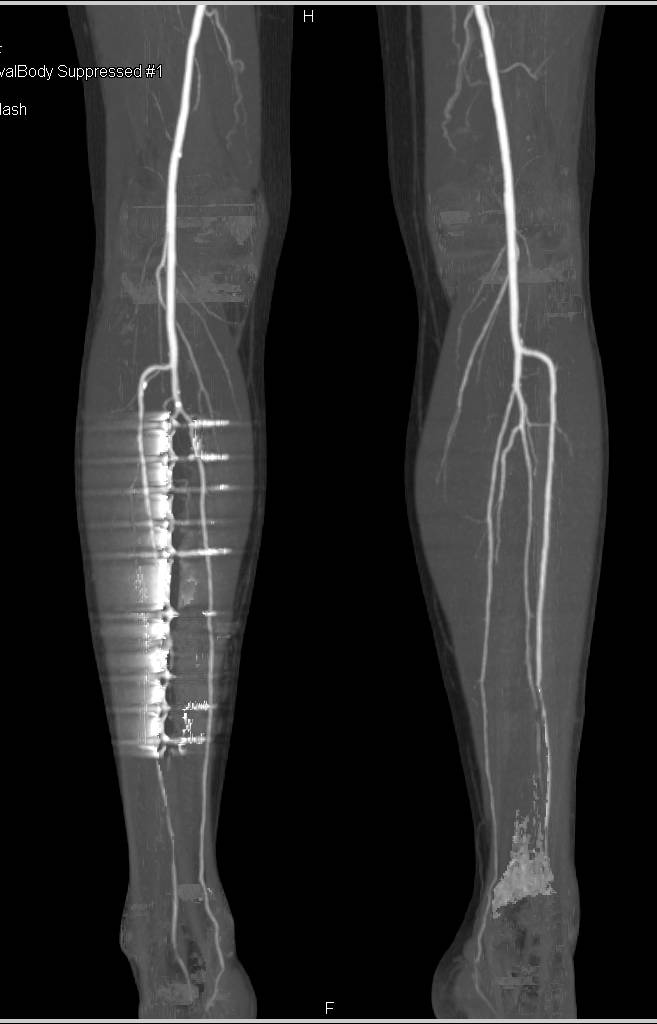

Aorto-Femoral Bypass Grafts and Runoff with Peripheral Vascular Disease (PVD) Nicely Demonstrated in 3D